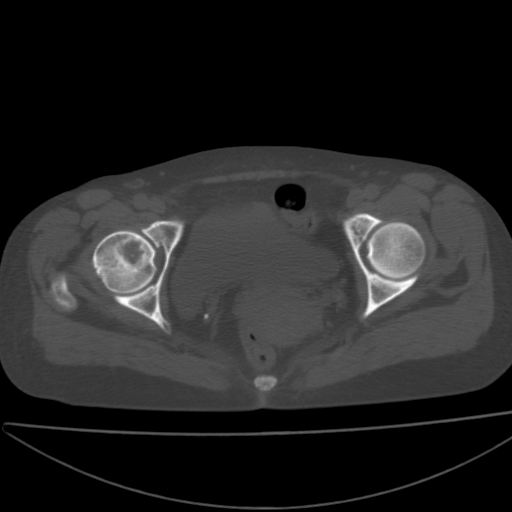

以下是引用xiaoniu在2008-9-6 8:22:00的发言:[br]右侧股骨颈囊性低密度,囊壁边缘硬化,中年妇女,首先考虑:骨囊肿。其次考虑动脉瘤样骨囊肿。[br][br][br][本贴已被 xiaoniu 于 2008-9-6 9:04:54 修改过]